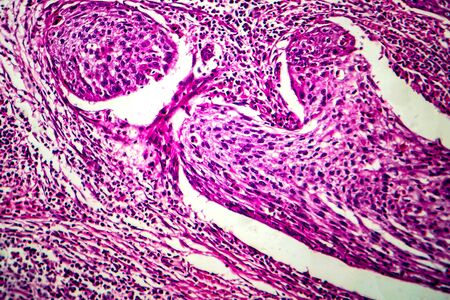

Condyloma acuminatum, also known as genital warts. Light micrograph, photo under microscope